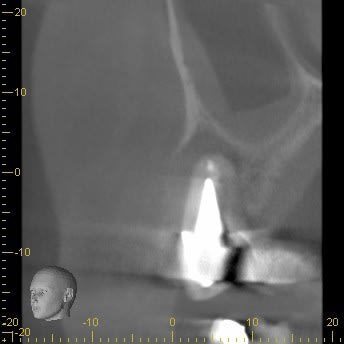

Je dois réaliser un comblement de sinus par voie crestale (Summers)au niveau de la 15 que j'ai extraite en septembre dernier suis à une fêlure ancienne et un kyste volumineux, d’où la perte osseuse.

Je viens de refaire un cône beam, mais la muqueuse sinusienne reste épaisse.

Je précise que la 16 est bien vivante, j'ai vérifié. La première radio montre la 15 avant extraction en septembre, la seconde la muqueuse à ce jour.

Montre nous une coupe 3D après cicatrisation mais cela semble hyper favorable. La muqueuse est épaissie mais sans plus, ce qui t'évitera de déchirer et maintiendra ton biomatériau. Pour moi, le cas est idéal pour un Summers. Je crains les muqueuses fines de sinus bien clair car c'est très très fragile. Attention aux images en plan type panoramique où tu crois avoir une hauteur d'os de folie comme sur ton cliché alors que ce n'est que la projection d'os du palais. En réalité, tu as beaucoup moins sur la crête. Tu le confirmeras par la 3D sur site cicatrisé.

Il n'y a que 5 ou 6 mn d'os disponible car la corticale vestibulaire a fondu avec le kyste.

J'ai repoussé l'intervention au mois de mars, mais je ne pense pas qu'il y aura une amélioration , car entre septembre (quand j'ai fait l'extraction de 15) et maintenant je n'ai quasiment aucune différence, alors que j'ai extrait la dent et cureté le kyste.